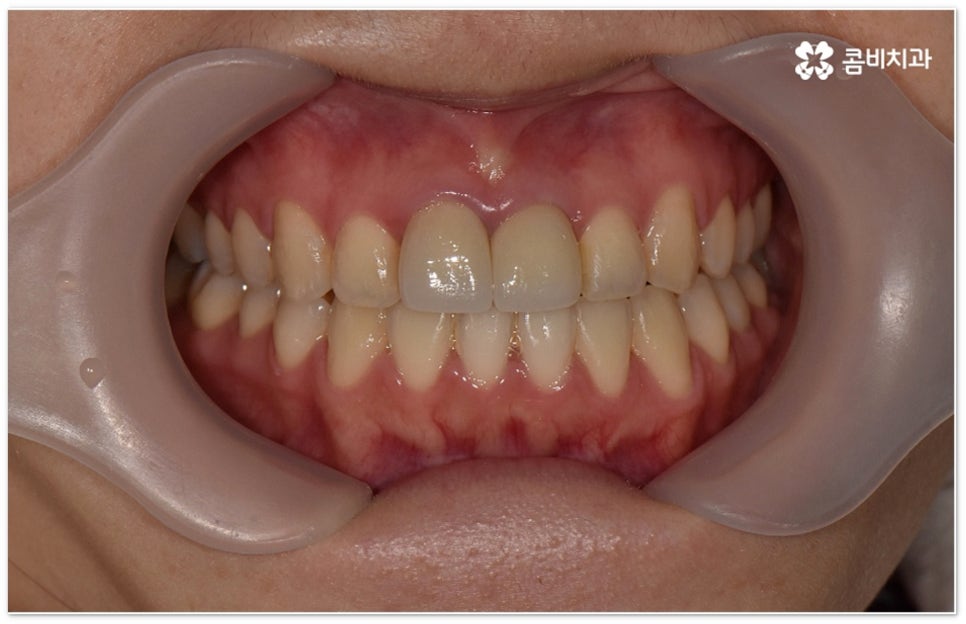

희고 가지런한 치아를 드러내며 환하게 웃는 사람을 보면 자기도 모르게 호감이 가곤하죠, 이처럼 대인 관계에서 치아는 좋은 인상을 만드는 데 심미적으로 큰 역할을 할 뿐 아니라 식사시 음식물을 저작하고 발음을 제대로 하는 데도 많은 도움을 주기 때문에 만약 타고난 치아가 삐뚤어졌거나 위아래 교합이 제대로 맞지 않는다면 이를 기능적 심미적으로 바로잡아 주기 위해서 치아 교정 치료를 고려해 볼 수 있습니다.

부정교합을 개선할 때 교합이 어긋난 정도가 심하고 구조적인 원인이 커서 부분 교정이 아닌 전체 교정이 필요한 케이스인 경우라고 해도 말씀드렸던 클리피씨 교정 장치 또는 보다 심미성을 강조한 치아교정장치 들의 도움을 통해 다른 사람과 얘기를 하거나 음식을 먹을 때 브라켓이 두드러지게 드러나는 부담을 줄일 수 있으니 설측교정, 콤비교정, 투명교정, 인비절라인 등에 대해서 한 번 알아보시고 각자에게 맞는 방법으로 교정 치료를 시작해 보시길 권유드리고 있어요.